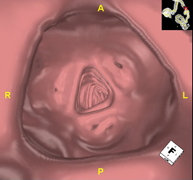

- Colonoscopia virtual

La colonoscopia virtual es una técnica no invasiva que permite la visualización tridimensional y bidimensional del intestino grueso o del colon mediante la toma secuencial de imágenes captadas con TC Multidetector de última generación. La calidad de las imágenes permite la navegación virtual por el interior del recto y del colon gracias al procesamiento en estaciones de trabajo especializadas. La preparación de la prueba consiste en realizar una dieta baja en fibra tres días antes de la prueba (para limpiar el colon y el recto) y de la ingestión de contraste oral yodado el día antes de la prueba (para marcar las heces y poder distinguirlas correctamente de las posibles lesiones colónicas). A diferencia de la fibrocolonoscopia, no se requiere sedación ni soluciones evacuantes. La prueba se realiza en la sala del TC donde, a través de un pequeño tubo flexible, se insufla aire para distender el colon.